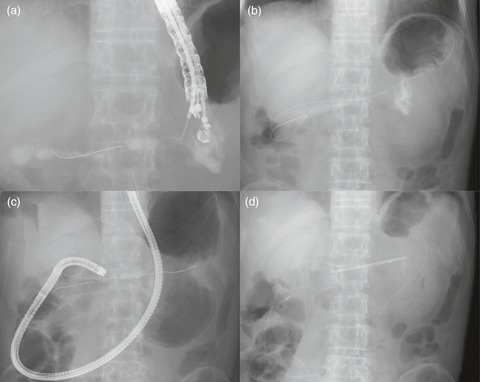

We investigated the efficacy and safety of surgery and external beam radiotherapy (EBRT), in patients with hepatocellular carcinoma (HCC) involving the inferior vena cava (IVC) and/or right atrium (RA) through a comparative meta-analysis. A systematic search of PubMed, MEDLINE, EMBASE, and the Cochrane library was performed for entries until July 2020. Eighteen studies with 22 cohorts were included, encompassing 755 patients. The pooled median overall survival (OS) and 1- and 2-year OS rates were 14.2 months, 55.6%, and 27.4%, respectively. The pooled median OS in the surgery and EBRT arms were 15.3 and 11.7 months, respectively. The pooled 1-year OS rate in the surgery arm was significantly higher than that in the EBRT arm (62.4%, 95% CI: 53.8%-70.3% vs 48.8%, 95% CI: 40.9-56.8, respectively; P = .023), while the 2-year OS rates were similar (27.5%, 95% CI: 19.7%-37.1% vs 26.9%, 95% CI: 20.7-34.2, respectively; P = .913). In the surgical arm, the perioperative mortality and grade ≥3 complication rates were 0%-7.6% and 3.9%-67%, respectively. Grade ≥3 complications and radiation-induced liver disease were rarely observed in the EBRT arm. Surgery could be an effective local modality for achieving the best survival rate, though it requires efforts to minimize morbidities and careful patient selection. EBRT, as a noninvasive modality, is a valid palliative option, especially for high-risk patients with a shorter life expectancy.